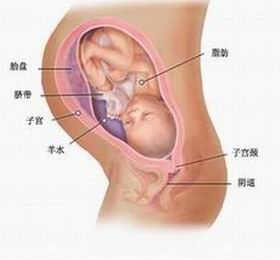

母体变化:从这时开始,孕妈妈到了怀孕过程中最为烦恼的时候。因为子宫继续在往上、往大长,子宫底的高达至 28—30 厘米,已经升到心口窝。因此,心脏被挤得不能像以往那样自由自在地活动,胃被挤得消化液分泌减少,而且,越来越沉重的子宫压在膀胱上。这一切,使得孕妈妈常常感到喘不过气来,并且心跳加快,食欲开始减退,尿频更加明显了,甚至好多地方还长出静脉瘤。由于腹部还在向前挺进,加之身体变得更为沉重,所以孕妈妈行动笨拙,有时,一不留意便引起腰部外伤,很容易使腰椎间盘突出。

33 周的时候,如果您是初产妇,这时候宝宝的头部已经降入骨盆,紧紧的压在子宫颈上;而对于经产妇,胎儿入盆的时间会较晚些。产妇此时手脚,腿等都会出现水肿,因此您要注意水的摄入量。对于水肿情况严重的孕妇,要及时到医院看医生。

34 周的时候,您也要注意以下的情况。如果您是初产妇,这时候宝宝的头部已经降入骨盆,紧紧的压在子宫颈上;而对于经产妇,胎儿入盆的时间会较晚些。产妇在此时手脚,腿等都会出现水肿,因此您要注意水的摄入量。对于水肿情况严重的孕妇,要及时到医院看医生。

35 周的时候,孕妇可以在胎儿在您腹中活动时看到宝宝手脚、肘部在腹部突显的样子,这是因为子宫壁和腹壁已经变得很薄的缘故。由此可以知道,光亮照进腹部的时候,宝宝会开始活动,到了晚上的时候,宝宝也会休息,逐渐的建立起了宝宝的每日活动周期。

36 周的时候,孕妇会感到下腹部坠胀,这主要是由于宝宝在妈妈腹的位置在逐渐下降。也是宝宝在妈妈腹部的位置在逐渐下降,孕妇前一阵子的呼吸困难和胃部不适等症状在本阶段开始缓解。但是随着体重的增加,孕妇的行动越来越不方便,有的孕妇甚至会时时有宝宝要出来的感觉。另外有的孕妇还会经常有尿意。这些都是正常现象,不必担心。